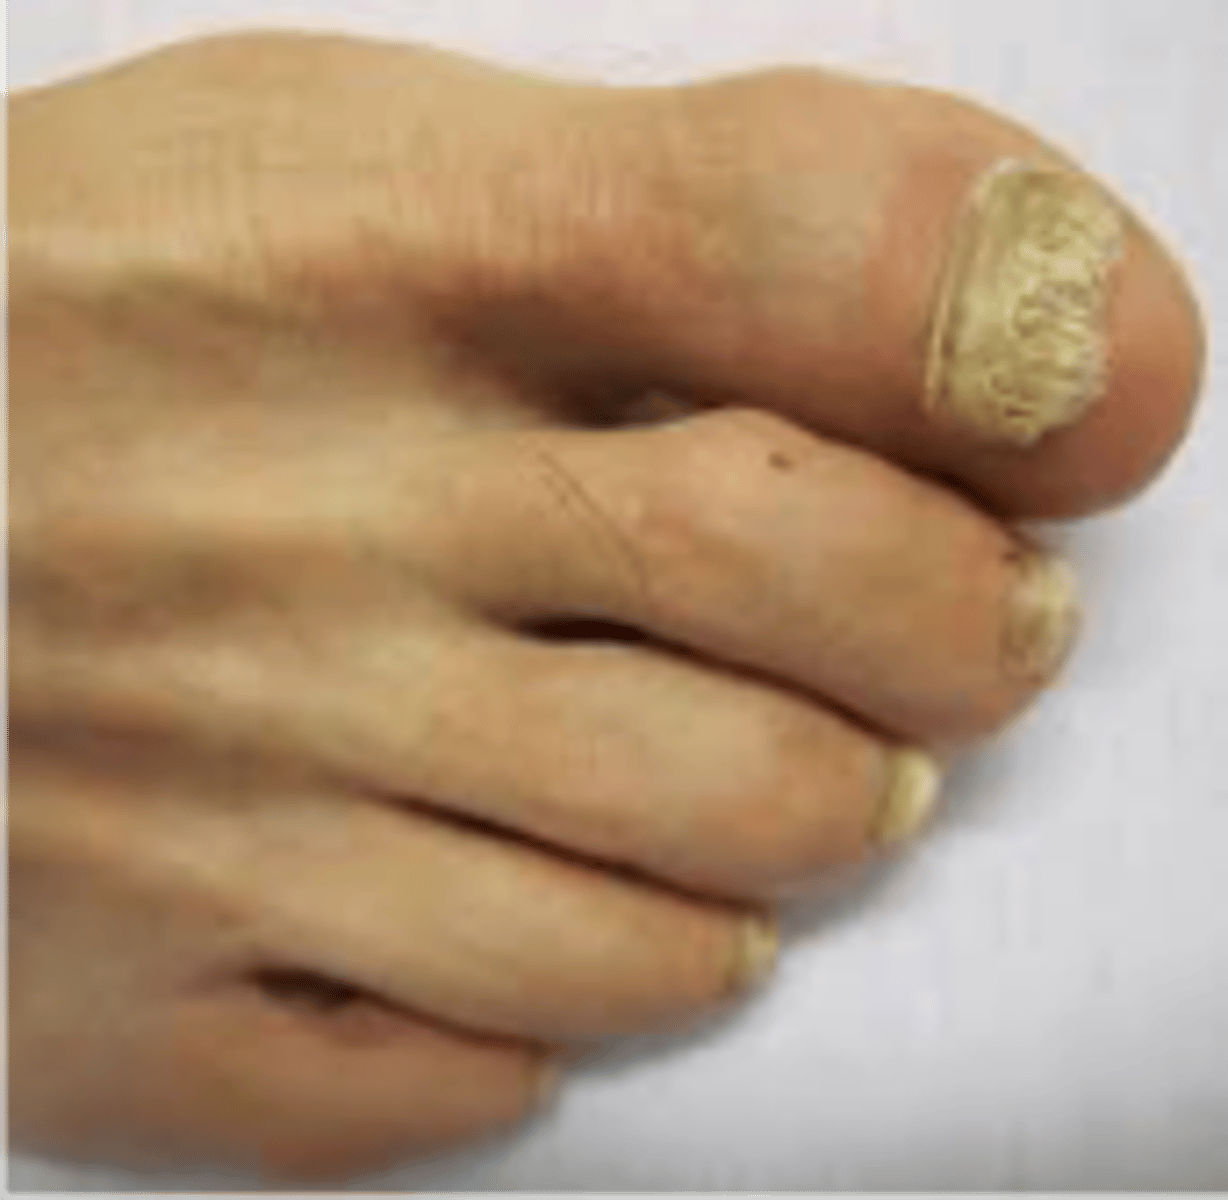

Onychomycosis

<p>◦Thickened yellow hypertrophic nail growth due to fungal infection</p>